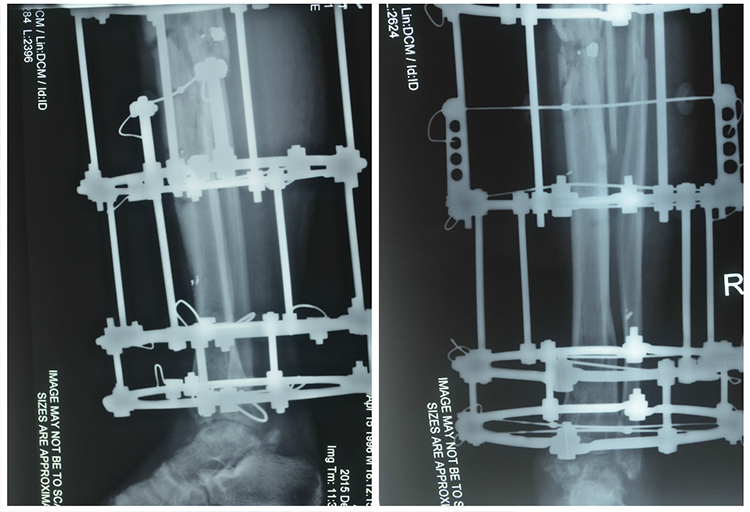

Допомогли в одужанні хлопцю лікарі проекту "Біотех-реабілітація поранених", куди він потрапив у важкому стані. За три місяці лікування традиційними методами у державних медичних установах великогомілкова кістка не зрослась. Крім того, кістка була від початку неправильно співставлена, тому у разі зрощення нога була б вивернута назовні. Також у Ігоря почався асептичний некроз таранної кістки. Це загрожувало загибеллю тканин кістки і, як наслідок, непрацюючим суглобом та вкороченням ноги.

Лікування новітніми методами для хлопця розпочалось у січні 2016 року. Основну операцію лікарі провели вже 16 березня, коли хлопцю ввели 3D-гель з чипсами остеопластичного матеріалу та аутологічними стовбуровими клітинами.